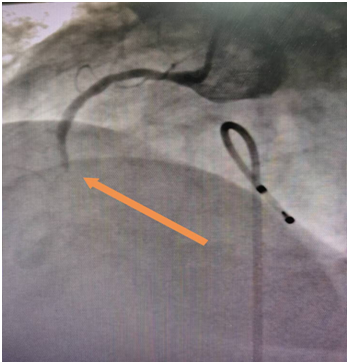

植入临时起搏器后,患者心率维持在起搏心率60次/分,为急诊支架植入术提供强有力的保障,避免术中猝死。急诊冠脉造影提示右冠状动脉急性闭塞,造影图示:

植入支架后患者右冠恢复血流,患者胸痛缓解,复查心电图未见房室传导阻滞。该患者为开阳县人民医院首例临时起搏器保驾下急性心肌梗死支架植入术,标志着该院心内科介入治疗水平明显提高,具备急诊支架植入术的能力。